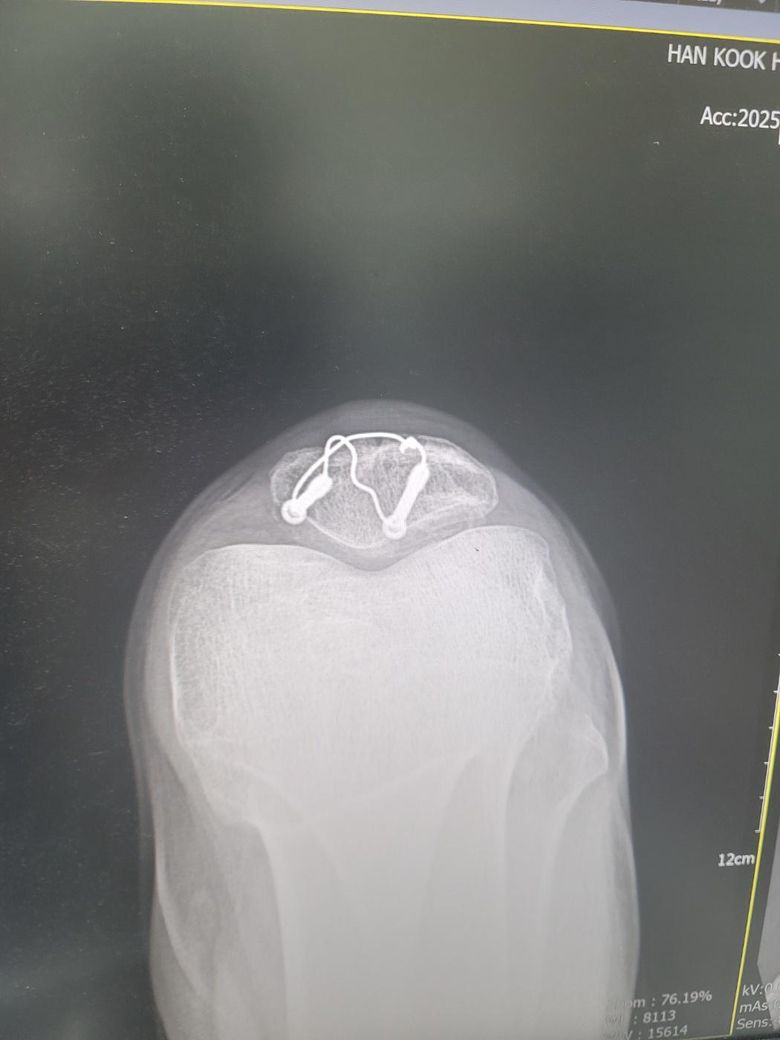

엑스레이 사진은 어제찍은 12주차 사진입니다

1. 엑스레이상 문제는 없나요?

2. 무릎에서 바깥부분부터 가로로 중간부분이 골절선처럼 움푹파여서 만져봐도 움푹파여있던데 뼈가 녹았다거나 생기다가 말수도 있는건가요? 참고로 분쇄골절입니다 ㅠㅠ

사진상으로 12주차라면 분쇄골절 회복 중인 상태로 보이고 금속 고정장치가 잘 자리 잡혀 있는 것으로 확인되어 보여요

무릎 바깥쪽 움푹 패인 부분은 골절 부위의 골융합이 아직 완전히 진행되지 않아 나타나는 정상 회복과정일 수 있습니다.

뼈가 녹았다기보다는 아직 뼈가 재형성중이거나 골편 사이가 완전히 매워지지 않은 상태로 볼 수 있습니다!

사진상 정확한 상태 파악이 어려울 수도 있지만 금속 핀 고정은 유지되어 있으며 골절 편들이 비교적 잘 맞춰져 있는 것으로 보입니다. 분쇄골절의 경우 뼈가 완전히 붙는 데 시간이 오래 걸리며 12주차 라면 아직 골소주들이 선명하게 연결되지 않은 상태로 특별한 핀 이탈이나 심한 전위가 없다면 큰 문제는 없을 것으로 생각됩니다.

무릎 중간 부분이 움푹 패여 보이는 것은 수술 후 연부조직의 위축 때문에 패여 보일 수 있으며 골절 부위의 고나절면이 함몰된 경우에도 패임이 느껴질 수 있습니다. 뼈가 녹았다기보다는 골절 치유 과정에서 흡수 재형성이 일어나거나 관절 연골의 손상 때문에 패여 보일 가능성이 있다고 생각합니다.